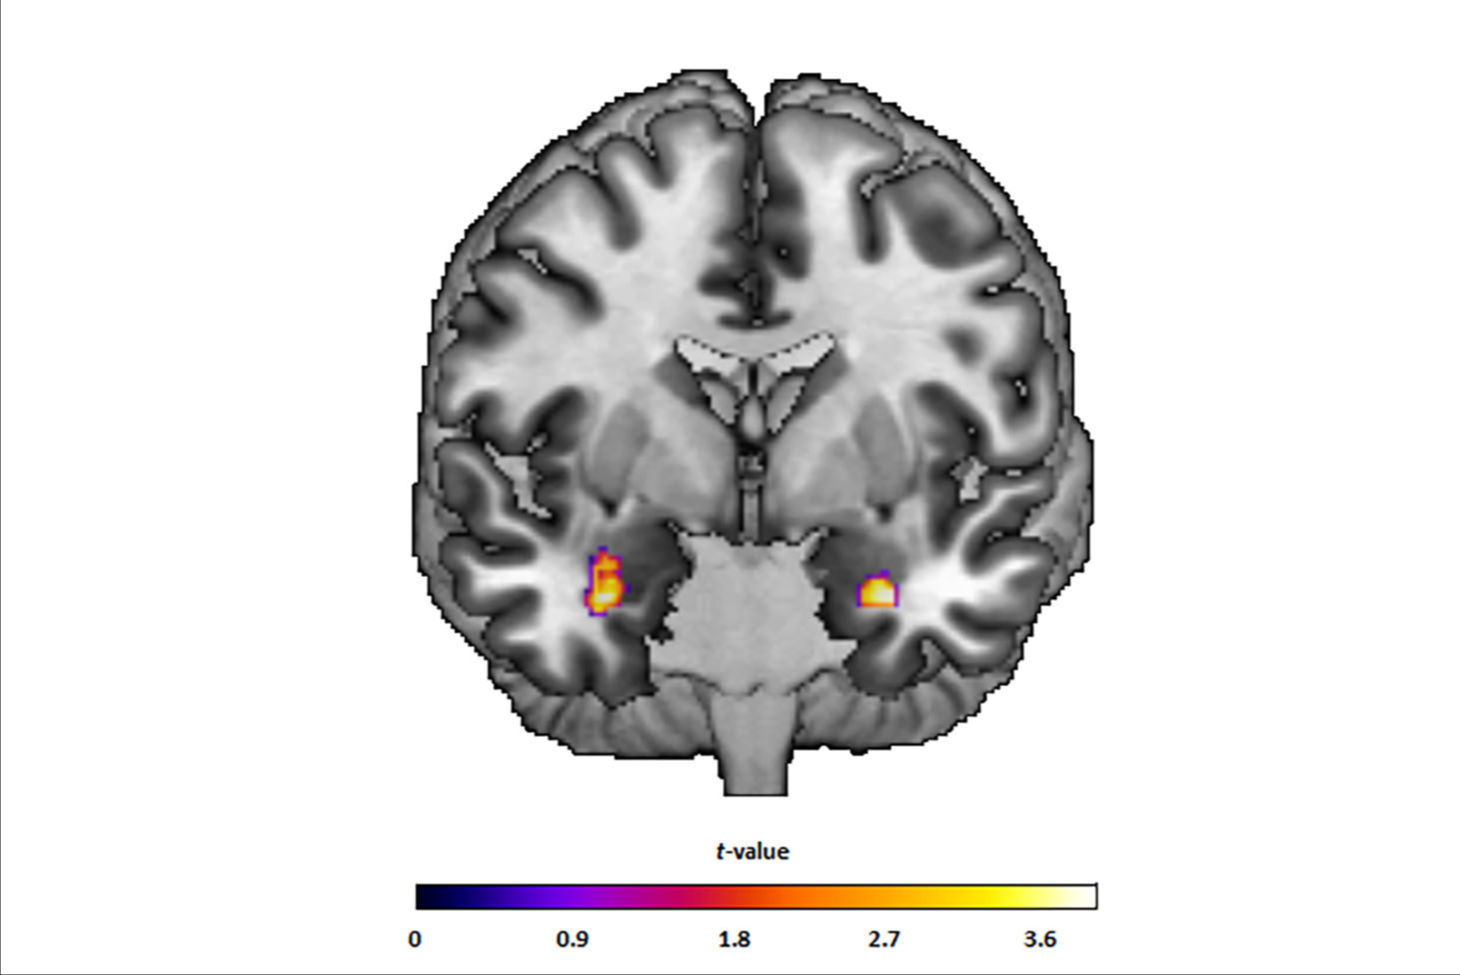

Coronal and axial slice of the average cortical F-18 MK-6240 SUVR [standard uptake value ratio] image for each study population. SUVR images were corrected for partial volume effects and masked with the gray matter mask used for volume of interest delineation. Overall tau accumulation is comparable between the late-life depression (LLD, middle column) and non-depressed cognitively unimpaired comparison (HC, left column) groups, while abnormal tau accumulation, which is most pronounced in the mesial temporal lobe, can be seen in the mild cognitive impairment due to Alzheimer's disease group (right column). Image and caption courtesy of the American Journal of Geriatric Psychiatry.

According to the findings, compared to non-depressed participants, late-life depression patients showed lower GMV in temporal and anterior cingulate regions, but similar tau accumulation and amyloid positivity rates.

In contrast, MCI patients had significantly higher tau accumulation in all regions. Moreover, tau did not correlate with any neuropsychological test scores in late-life depression patients, the researchers wrote.

“Our findings suggest [Alzheimer's disease]-type tau is not higher in [late life depression] compared to non-depressed, cognitively unimpaired older adults and appears unlikely to contribute to lower gray matter volume in LLD,” the authors wrote.